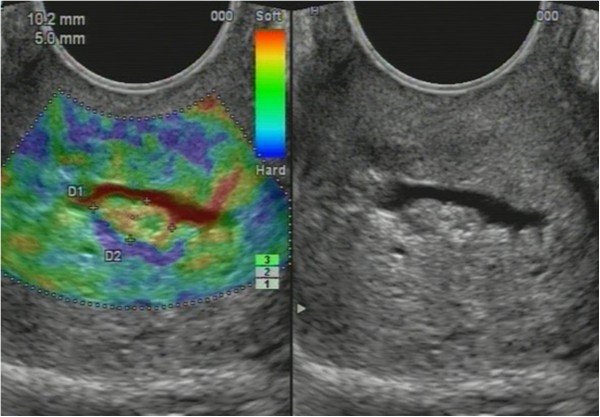

Non-homogenous and irregular margins were significantly higher in AEH than in both groups (P < 0.01). Mean M-echo thickness was found to be non-significant. Hypoechoic areas, hypervascularity on Doppler imaging, and stiffness (Figures 14 and 15) were more specific for AEH than for glandular cystic hyperplasia (P < 0.01, P < 0.01, P < 0.01, respectively; Figure 16). Fluid in the uterine cavity and BGR artefact were found to be specific for AEH (P < 0.01; Figure 17); BGR appearance correlated to the presence of fluid in the uterine cavity (r > 0.97; Figure 18).

Figure 15

Sonoelastography of endometrial lesion. Soft pattern on SEG helps to exclude the polyp.